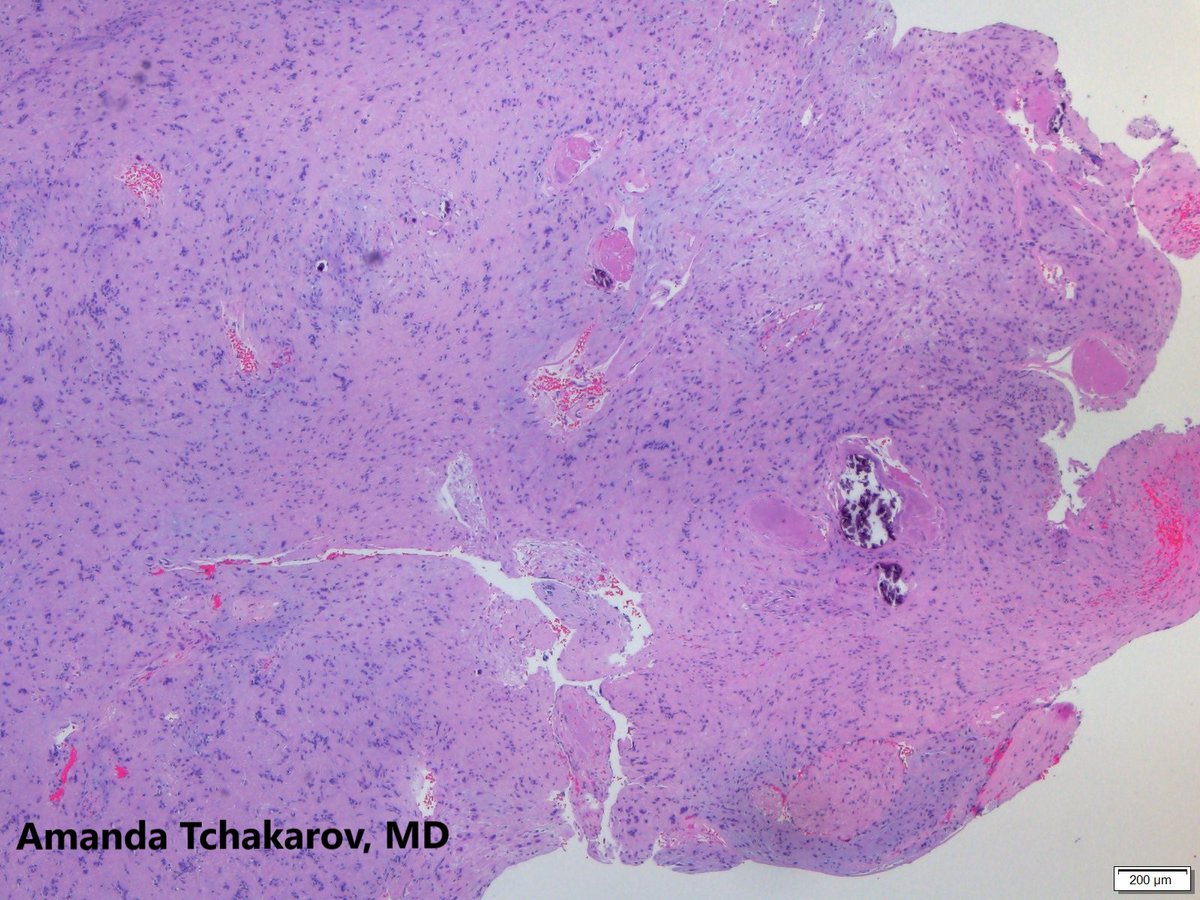

@UTHoustonPath

UTHealth Houston Pathology

1 year

Neck mass in a teenager. Diagnosis? @ATchakarov1 #PathTwitter #Pedipath #Pathology #PathX #PathResidents